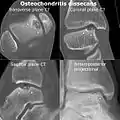

Computed tomography (CT) scans and Technetium-99m bone scans are also sometimes used to monitor the progress of treatment. Unlike plain radiographs (X-rays), CT scans and MRI scans can show the exact location and extent of the lesion.[39] Technetium bone scans can detect regional blood flow and the amount of osseous uptake. Both of these seem to be closely correlated to the potential for healing in the fragment.[40][41]

CT scan and projectional radiography of a case of osteochondritis dissecans of parts of the superio-medial talus.

Sagittal MRI: Linear low T1 signal at the articular surfaces of the lateral aspects of the medial condyle of the femur confirms the presence of OCD.